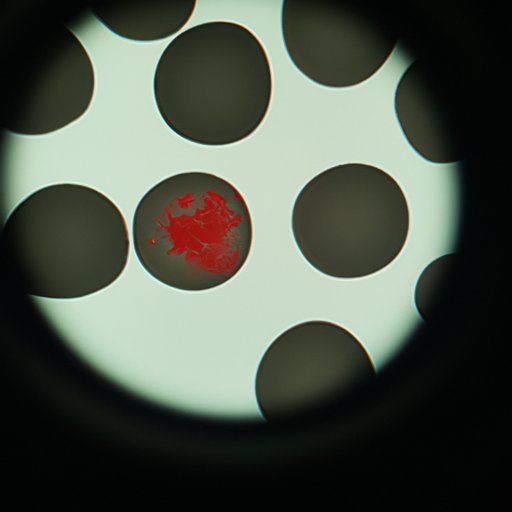

Overview of White Blood Cells

White blood cells are produced in the bone marrow and released into the bloodstream. They are much larger than red blood cells and have a nucleus, which gives them the ability to recognize foreign invaders and attack them. White blood cells are also able to produce antibodies, which are proteins that bind to foreign invaders and help to neutralize them.

Investigating the Role of White Blood Cells in Fighting Infection

White blood cells play an important role in fighting infection. When a foreign invader enters the body, white blood cells recognize it as foreign and attack it. They also produce antibodies, which bind to the foreign invader and help to neutralize it. This process helps to protect the body from infection and disease.